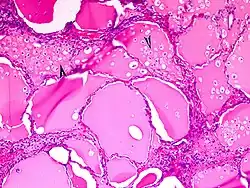

Histiocyten hebben gemeenschappelijke histologische en immunofenotypische kenmerken. Dat is door immunokleuringen aangetoond. Hun cytoplasma is eosinofiel en bevat wisselende hoeveelheden lysosomen. Ze dragen membraanreceptoren voor opsoninen, zoals IgG en het fragment C3b van complement. Ze brengen LCA's (leukocyte common antigens) CD45, CD14, CD33 en CD4 tot expressie, maar die worden ook door T-helpercellen tot expressie gebracht.

- Macrofagen zijn zeer variabel in grootte en morfologie, hun cytoplasma bevat in relatie tot hun gespecialiseerde fagocytische functie veel zure fosfatase bevattende lysosomen. Ze brengen CD68 tot expressie.

- Dendritische cellen hebben een ingedeukte, boonvormige celkern en cytoplasma met dunne uitlopers, dus dendritisch. Hun belangrijkste activiteit is antigeenpresentatie; ze brengen Factor XIIIa, CD1c en klasse II humaan leukocytenantigenen tot expressie.